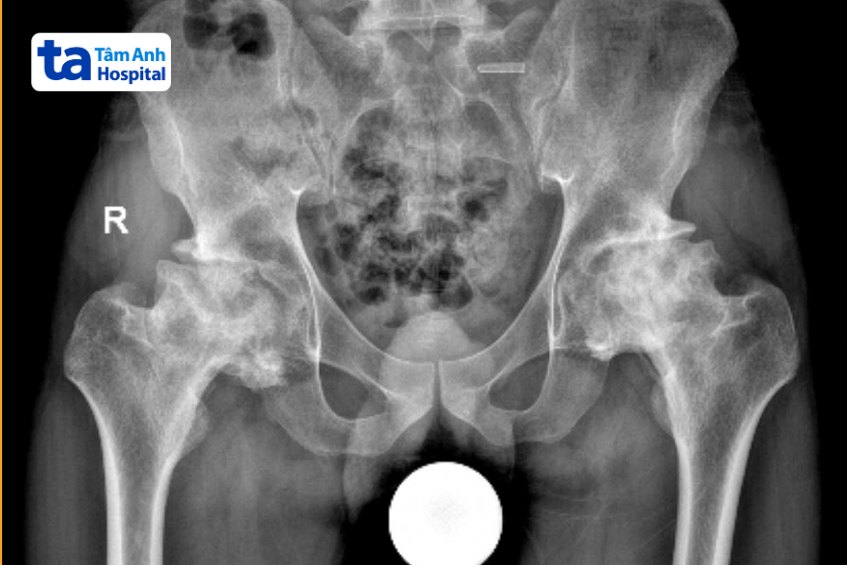

ThS.BS.CKI Đặng Khoa Học, Trưởng khoa Chấn thương Chỉnh hình Tổng quát, Bệnh viện Đa khoa Tâm Anh TP HCM, cho biết kết quả chụp MRI cho thấy tình trạng hoại tử chỏm xương đùi ở cả hai chân của anh Dũng đã tiến triển đến giai đoạn cuối, xuất hiện nhiều gai xương, gây cứng và biến dạng khớp, co rút cơ. Cách nay ba năm, anh Dũng có chỉ định phẫu thuật nhưng từ chối do lo ngại thay khớp sớm sẽ phải thay lại.

Kế hoạch phẫu thuật dành cho anh Dũng là loại bỏ gai xương, giải quyết tình trạng cứng khớp. Sau đó thay khớp háng nhân tạo và cân bằng lại chiều dài hai chân, giúp người bệnh lấy lại dáng đi, khôi phục khả năng vận động. Ngoài ra, hai thành phần khớp háng tự nhiên là ổ cối và chỏm xương đùi của người bệnh đều đã biến dạng.

Để đảm bảo khớp háng nhân tạo được đặt vào đúng chỗ, trước khi phẫu thuật, bác sĩ đã dùng phần mềm TraumaCad định vị lại vị trí khớp háng. Trong quá trình phẫu thuật, bác sĩ sử dụng C-Arm (hệ thống chụp X-Quang trong phẫu thuật) để kiểm tra vị trí đặt khớp và đảm bảo loại bỏ hết gai xương. Nhờ đó, khớp háng nhân tạo được đặt vào đúng vị trí như khớp háng tự nhiên, giúp người bệnh vận động thoải mái nhất có thể.